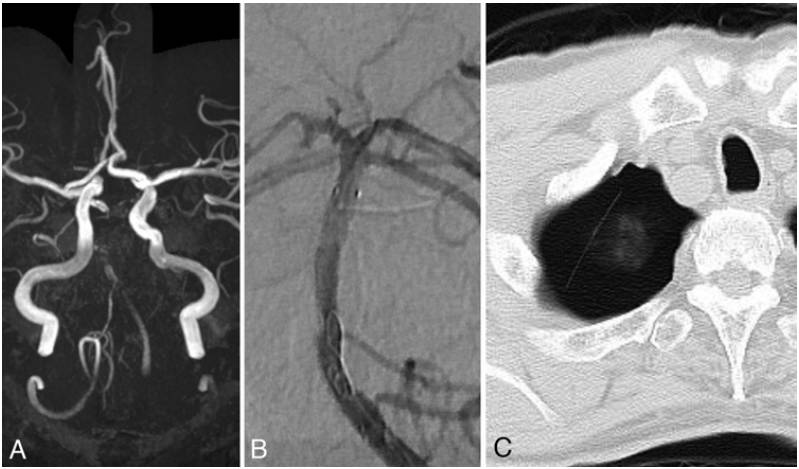

病例2,67岁男性患者,右利手;因“左侧肢体乏力和发音障碍2小时40分钟”入院。入院时,NIHSS评分9分,mRS评分3分;多模态头颅MRI显示,桥脑基底多处高信号改变,基底动脉干节段性闭塞(图2A),诊断为急性基底动脉闭塞。立即进行血管内介入术重建血流。术中顺利地将微导丝通过基底动脉干的闭塞段,在球囊扩张成型后将一枚Wingspan支架植入基底动脉干内。随后,DSA造影显示基底动脉远端有血栓残留,导致动脉管腔狭窄。即刻使用Agility导引导丝将溶栓用微导管输送至基底动脉远端,行局部溶栓治疗。接着,发现导引导丝与支架壁缠结,通过多种努力均无法将导引导丝撤回,只能将其留在体内。通过另一根微导丝撤出微导管(图2B)。术后4年患者出现胸痛,复查胸部CT显示,在右肺尖部肺气肿处的顶端出现不透射线的曲线物,其一端在纵膈上,另一端在后肋骨下角,伴随少量单侧胸腔积液(图2C),考虑是断裂的导丝迁移至右胸腔。最后,手术顺利取出导丝。

图2. 病例2的颅内MRA、DSA和胸腔CT的检查结果